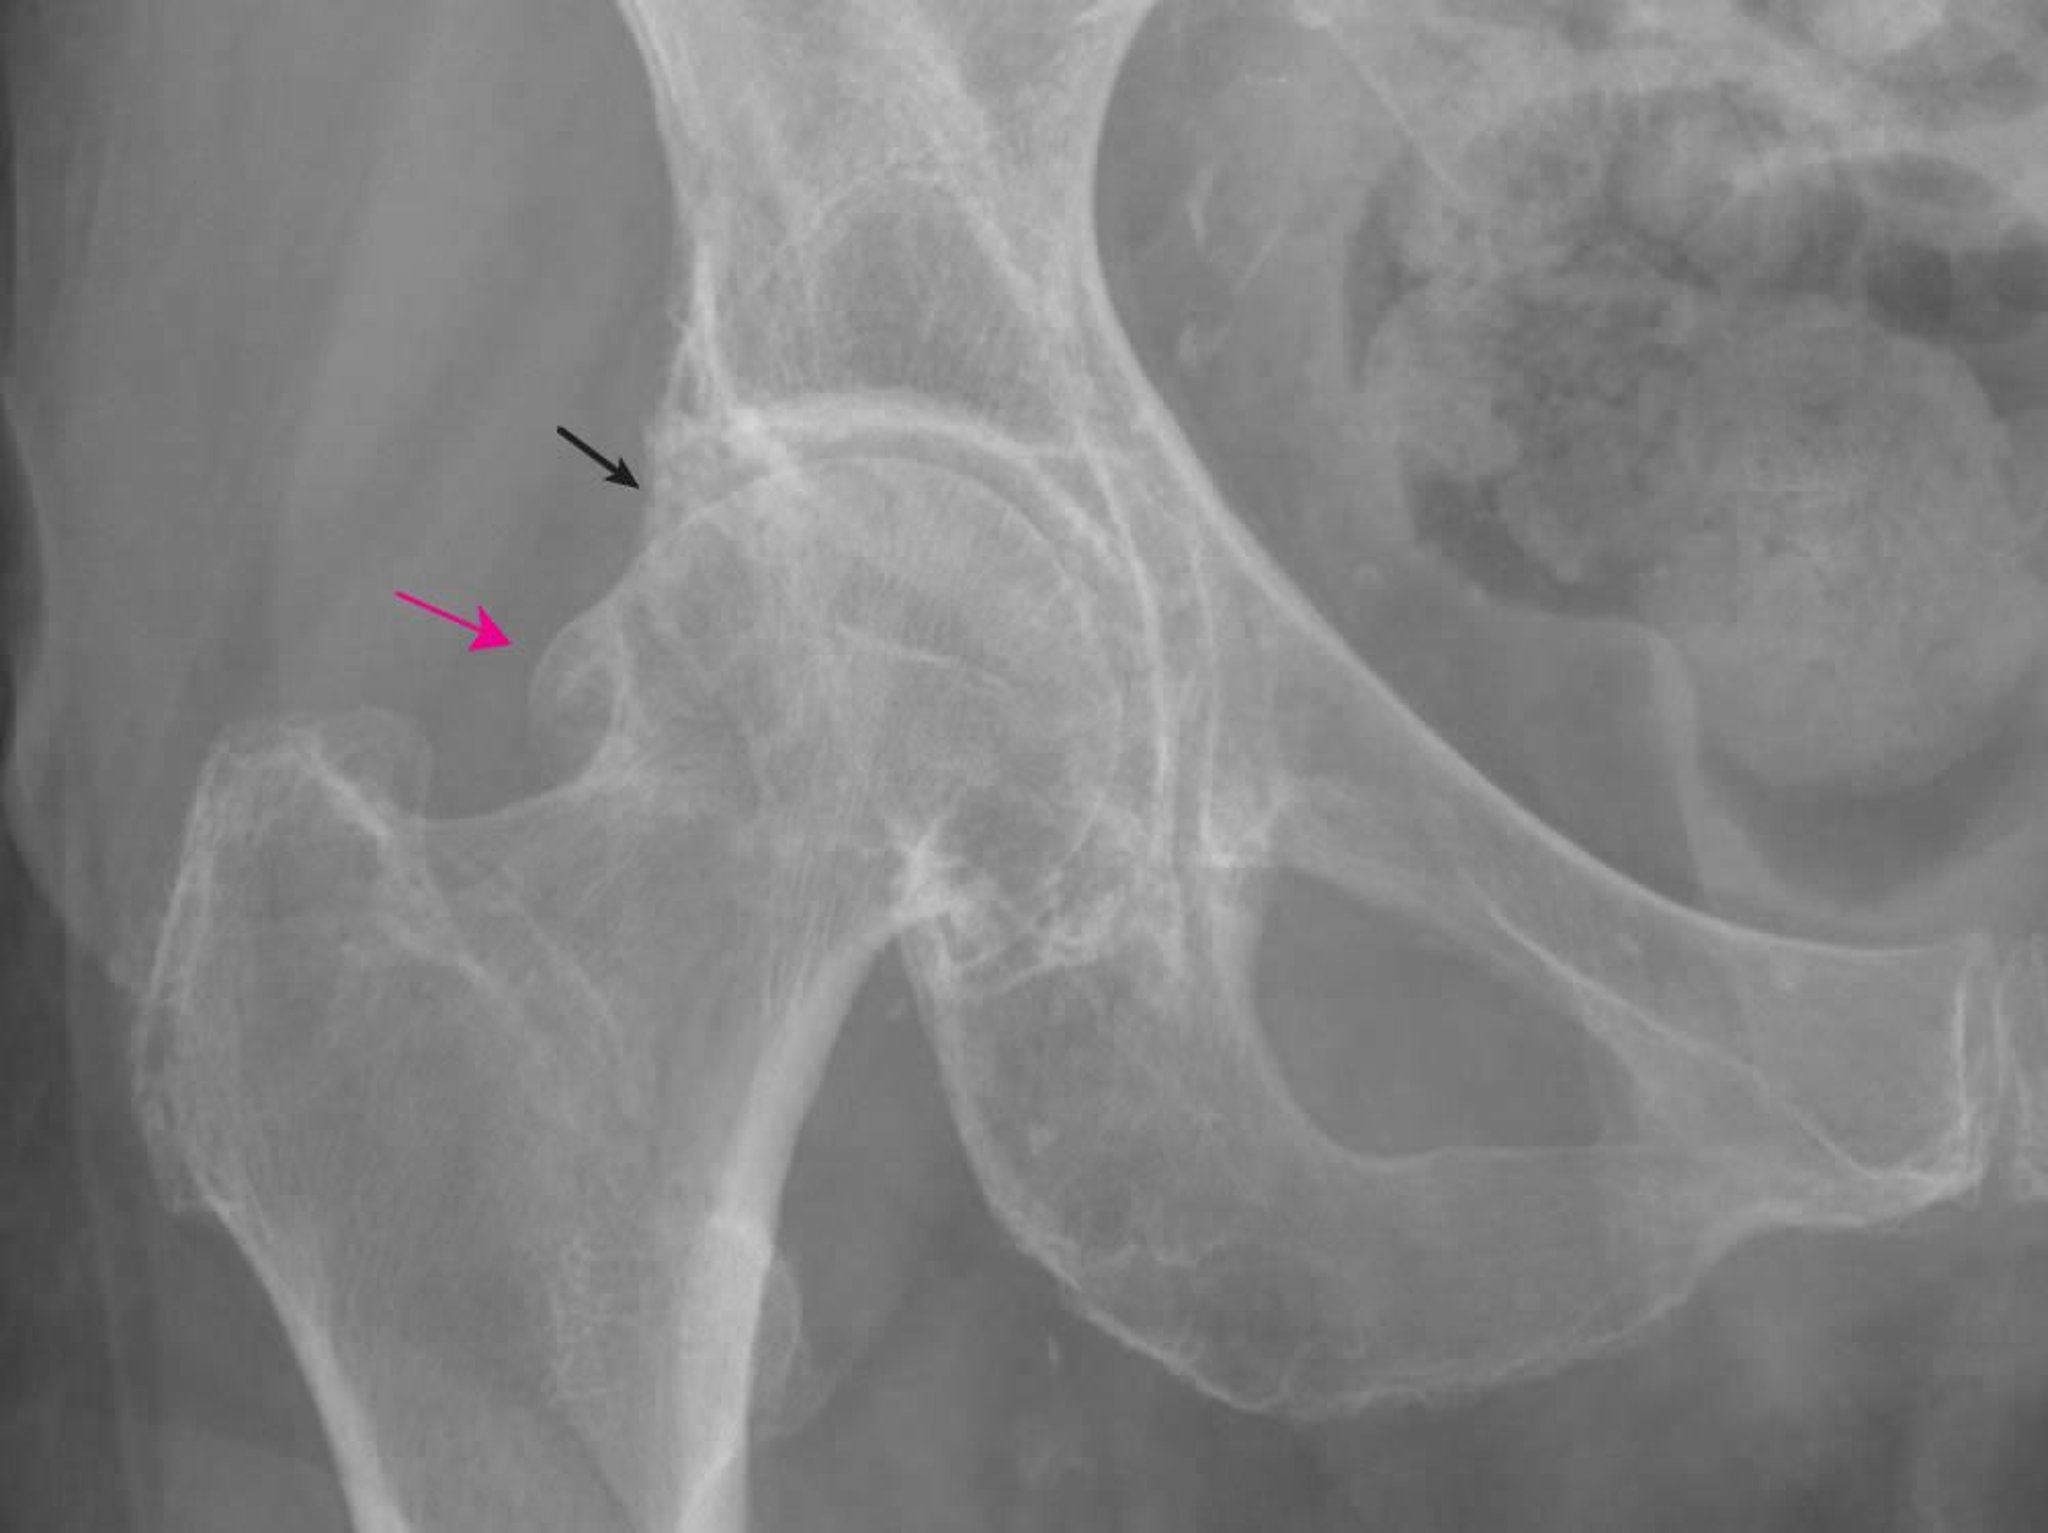

Questa radiografia mostra cambiamenti caratteristici dell'artrosi, inclusi grandi osteofiti femorali (freccia rossa) e acetabolari (freccia nera) e un restringimento dello spazio articolare.

Immagine fornita da Roy Altman, MD.